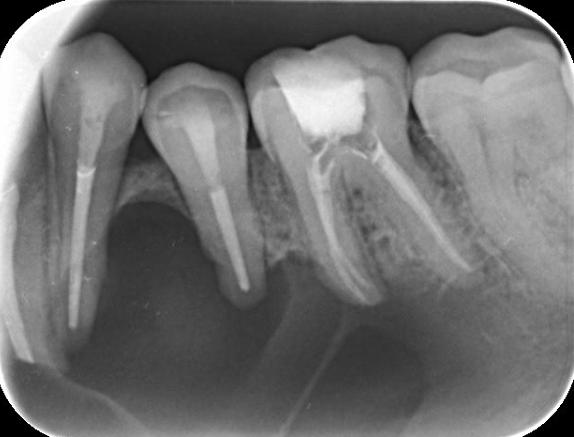

PERIAPICALES: (Intraorales)

Son radiografías de tamaño reducido que captan varios dientes o pequeñas zonas. Se introducen en el interior de la boca.